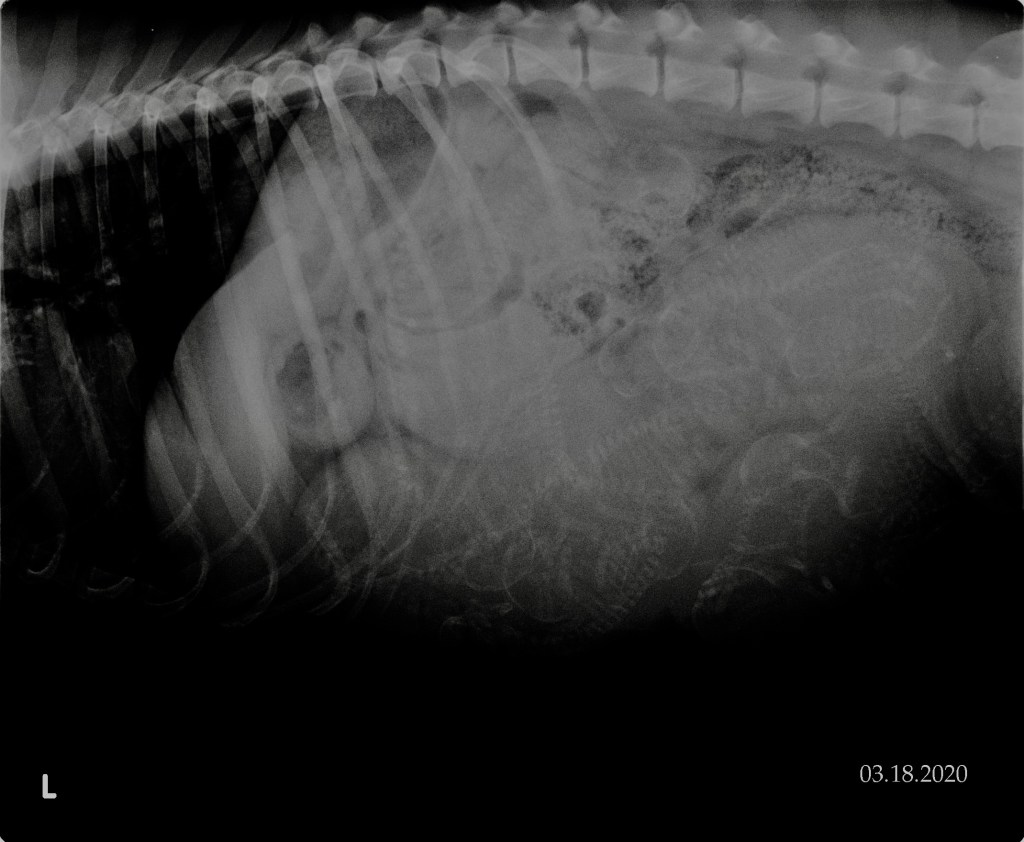

3-18-20

Today we had our repro vet take an x-ray and count how many little puppies she sees inside of Miss Kimb. Before she even took her back to take the picture, she said that she might have the pups sooner than her due date, which isn’t abnormal for a litter this size. She was pleasantly surprised when she saw how well she has been doing. When Dr. Harr came back into the room, she said that she saw 11 puppies for sure, and that maybe a 12th was hiding in there too!

Feel free to comment how many you see; don’t forget to check under her ribs too!